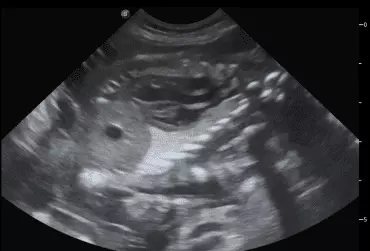

W literaturze opisano niewiele przypadków ciąż bliźniaczych jednokosmówkowych u suk. W trakcie wczesnej diagnostyki ultrasonograficznej ciąży u suki rasy whippet (chart angielski) zobrazowano pęcherz ciążowy, w którym znajdowały się dwa zarodki. Podczas badań kontrol­nych zarodki, a później płody wykazywały prawidłową organogenezę i żywotność. Ich rozwój przebiegał podobnie względem pozostałych ośmiu płodów. W 63. dniu ciąży wykonano zabieg cesarskiego cięcia i wydobyto dwa płody tej samej płci, o bardzo podobnym wyglądzie, z dwóch pęcherzy płodowych przyczepionych do jednego łożyska, oraz pozostałe osiem płodów.